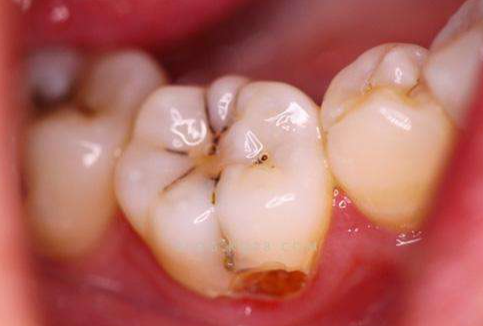

牙髓炎包括可復性牙髓炎和不可復性牙髓炎。

可復性牙髓炎是牙髓組織的初期炎癥,可由深齲、牙隱裂、深楔狀缺損、咬合創(chuàng)傷等引起,經過祛腐、調合、安撫治療兩周后,牙髓可能恢復健康狀態(tài),疼痛消失,則可行復合樹脂充填即可;若安撫治療無效,患牙出現(xiàn)疼痛加重,則需行根管治療。。

不可復性牙髓炎包括急性牙髓炎、慢性牙髓炎、殘髓炎、牙髓壞死、逆行性牙髓炎等,牙髓炎癥不可能通過口服消炎藥物逆轉修復,治療以保牙為主,應急止痛后行完善的根管治療,逆行性牙髓炎還應聯(lián)合牙周治療。